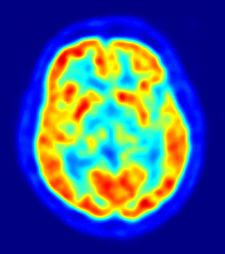

Científicos del Centro de Investigación en Imagen Clínica de la Universidad de Washington, en Estados Unidos, han mostrado en el 57 Encuentro Anual SNM, que se celebra en Salt Lake City hasta este miércoles, 9 de junio, sus progresos en el uso de imágenes PET para seguir las etapas tempranas de la enfermedad de Alzheimer. Este hallazgo podría llevar al descubrimiento de medidas preventivas que beneficiarán a millones de pacientes que sufren este desorden neurodegenerativo crónico.

En uno de los pocos estudios longitudinales realizados a gran escala sobre este fenómeno, los científicos usaron una tomografía por emisión de positrones (PET, por sus siglas en inglés) para documentar los cambios que se producen durante la acumulación de beta-amiloides, que forman placas en los tejidos neuronales de los pacientes a los que se les diagnostica Alzheimer.

El PET y otras técnicas de imagen molecular ayudan a los investigadores a entender el inicio de la patología para determinar el mejor tratamiento para cada paciente, incluso antes de que aparezcan síntomas como la pérdida de memoria, las dificultades para pensar o la habilidad para realizar tareas simples. Según Mintun, «con este tipo de investigaciones, los médicos podrán recomendar el tratamiento antes de que se den daños irreversibles en el cerebro del afectado».

Un total de 129 personas, con edades entre los 45 y los 86 años y sin síntomas de padecer un desorden cognitivo, participaron en este estudio. Se sometieron a escáneres con PET en un periodo de cinco años, usando el Pittsburgh Compound-B (11C-PIB), un agente de imagen PET que muestra los beta-amiloides en el cerebro.